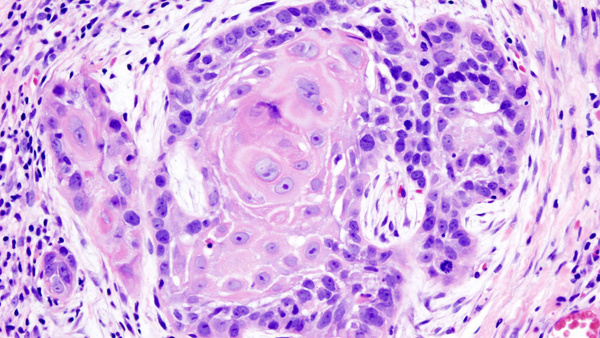

Клетки плоскоклеточного рака изо рта. Изображение © Flickr / Weining Zhong